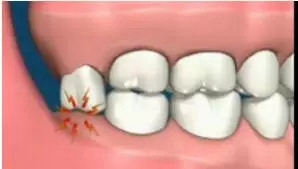

局部清潔死角引發(fā)齲齒

智齒萌出位置不正,即使沒有頂壞鄰牙,也可能與鄰牙形成間隙,產(chǎn)生局部的“衛(wèi)生死角”,食物殘渣和細菌堆積在這些部位,我們?nèi)粘K⒀篮茈y清潔到,久而久之就容易引發(fā)齲齒

640.webp (7).jpg